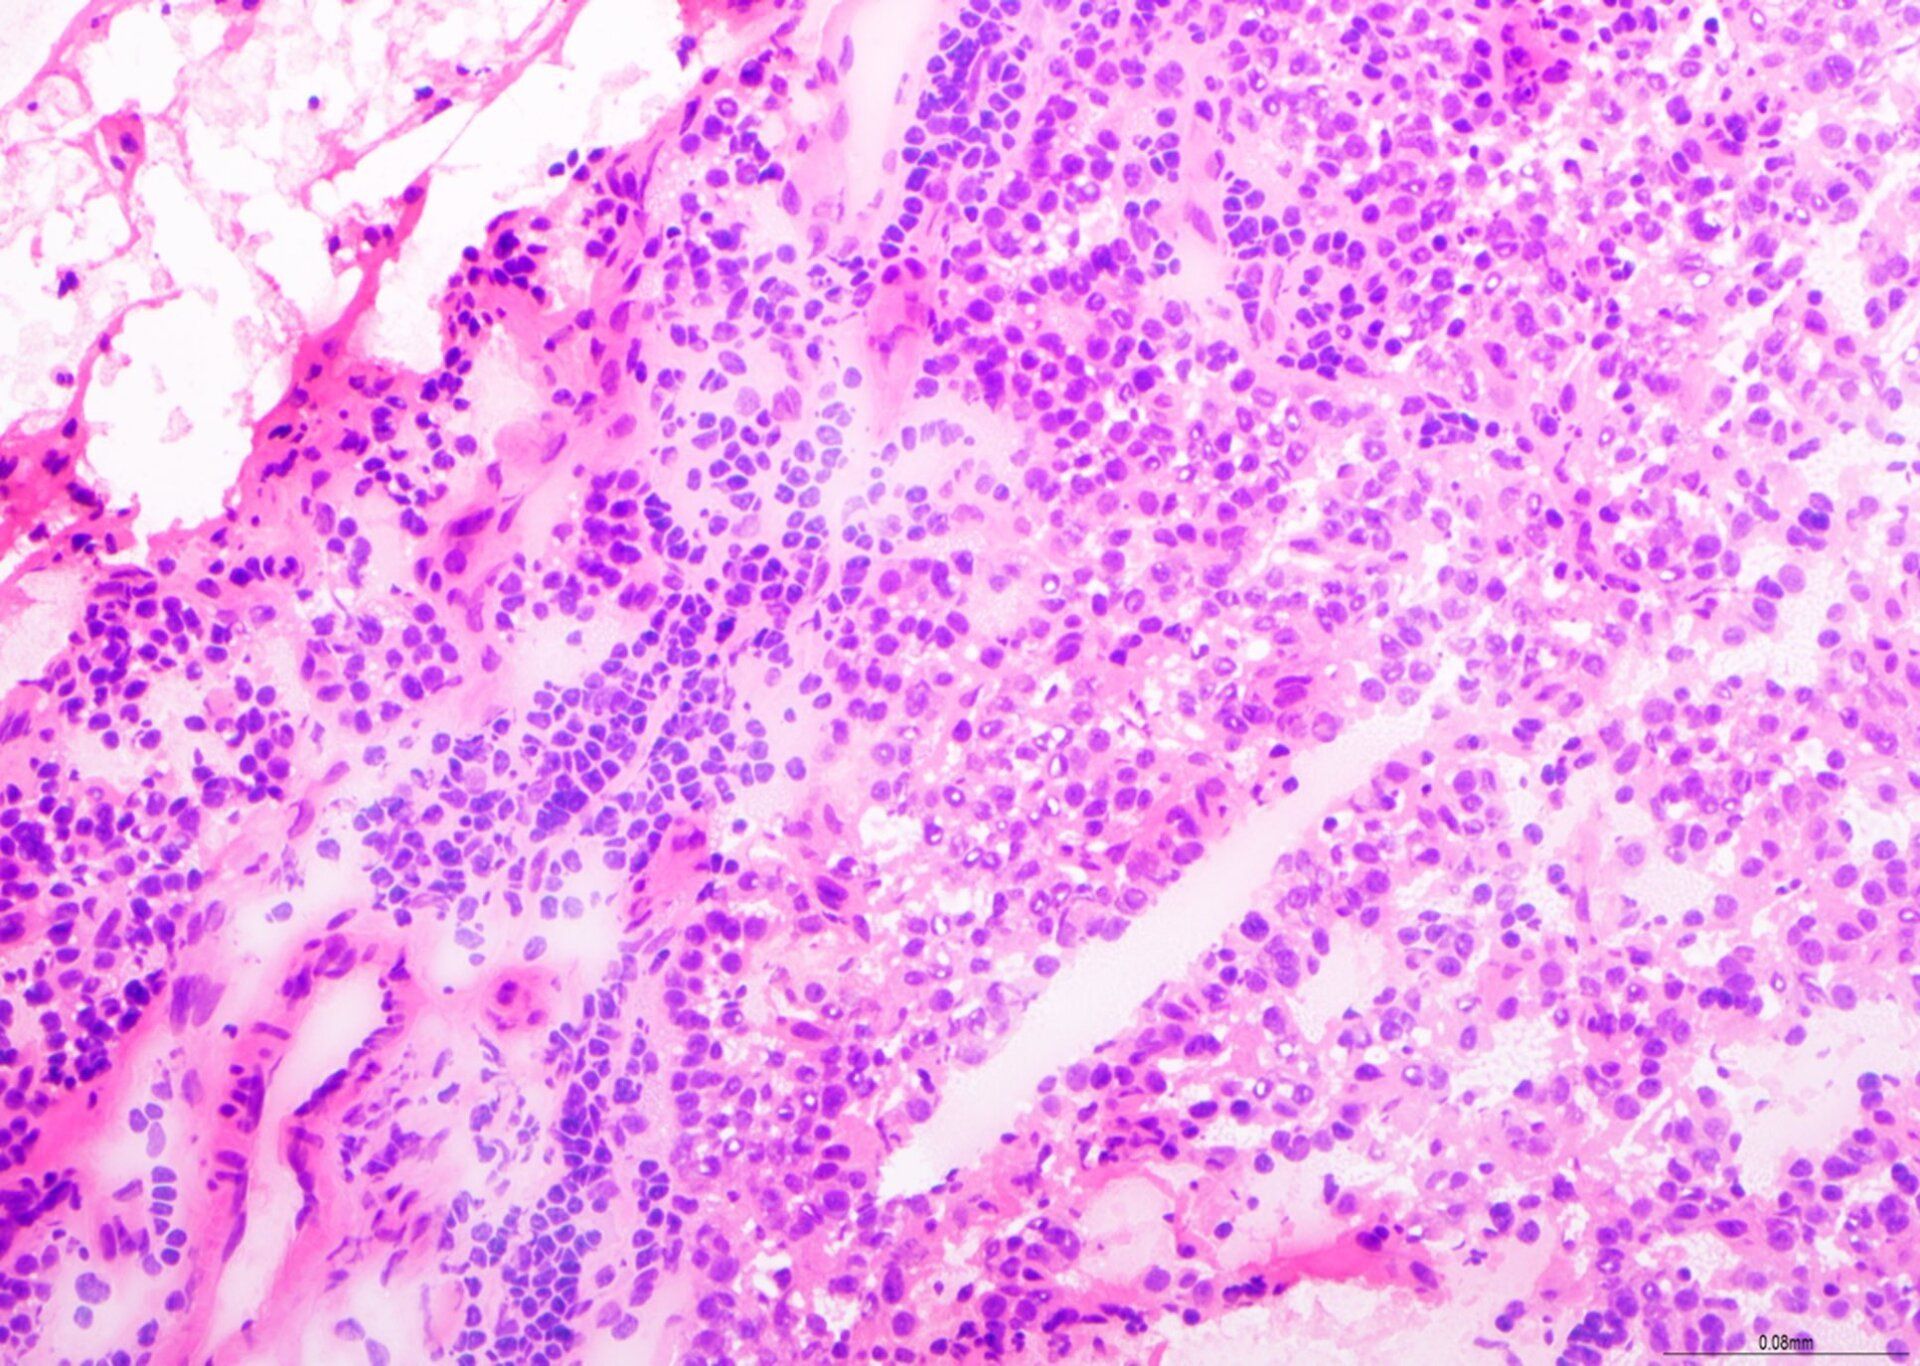

H&E - Πρόγραμμα BMT

Πρόκειται για μια εξαιρετική προετοιμασία βιοψίας BMT, με ισορροπημένη χρώση H&E, καλή λεπτομέρεια χρωματίνης και επιλεκτική χρώση κυτταρικών τύπων εντός του ιστού του μυελού των οστών. Αυτή η διαφάνεια βαθμολογήθηκε με 9/10 κατά την αξιολόγηση.